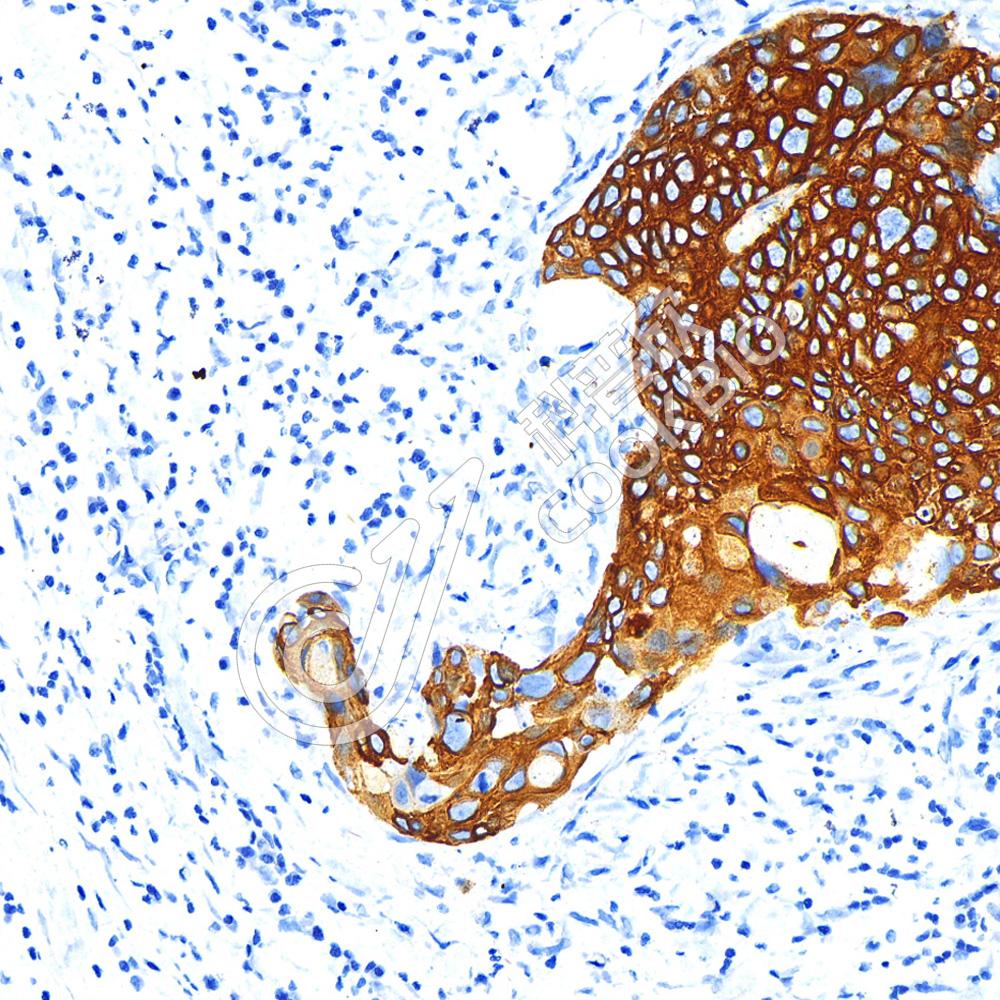

IHC检测Cytokeratin 10蛋白(货号 K1334239).

样品: 大鼠皮肤, 4%多聚甲醛 (货号KSG1101) 固定12-24小时.

抗原修复: 柠檬酸抗原修复液(干粉, pH 6.0) (KSG1201), 98℃, 20分钟.

—抗: 1: 2500稀释, 4℃ 孵育过夜.

二抗: S-vision免疫组化多聚二抗(山羊抗兔),即用型 (货号KB3906), 室温孵育20分钟.

样品: 大鼠胃, 4%多聚甲醛 (货号KSG1101) 固定12-24小时.